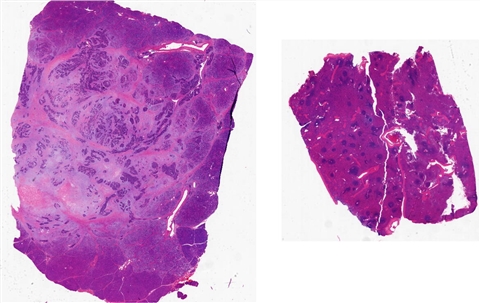

案例2 (6843)

患者详情: 因“反复便血一周“入院。患者1周前无明显诱因出现便血,为新鲜血液,大便为粘液血便,伴腹胀、头晕。外院肠镜:距肛门口4cm可见菜花样肿物,约3cm,宽基,组织脆弱易出血,表面糜烂,边界尚清,肠镜难以通过。病理提示:直肠恶性肿瘤,考虑为神经内分泌肿瘤。既往“高血压”10余年,其他无特殊。患者强烈要求局部切除。 临床诊断:直肠恶性肿瘤;高血压3级

取材部位: 直肠

大体所见: (直肠肿物)4 X 2.5 X 1.5cm灰黄肿物一个,表面粘膜粗糙增厚,切面灰黄灰红,肠壁结构观察欠清,实性质中,可见出血。

免疫组化: CK,CD56,CgA,Syn,SSTR2,Ki67

医院: 中山大学附属第三医院